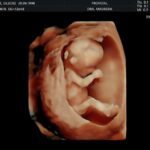

• Ecografía Morfológica Doppler (Semanas 16-26): Un estudio detallado de cada parte del cuerpo fetal (cerebro, corazón, columna, órganos y extremidades) para descartar anomalías estructurales.

• Ecografía de Crecimiento Doppler (Semanas 28-36): Evalúa el crecimiento fetal y la función placentaria para asegurar que el peso del bebé sea el adecuado para su edad gestacional.